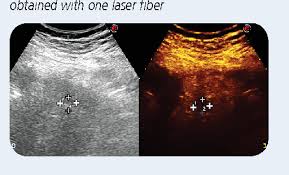

•A type of laser treatment called laser-induced interstitial thermotherapy (LITT) can be used to treat some types of tumors, such as certain tumors in the liver. It uses heat to help shrink tumors by damaging cells or depriving them of the things they need to live (like oxygen and food).

Below is the schematic diagram for different laser diodes set-up in medical industry: